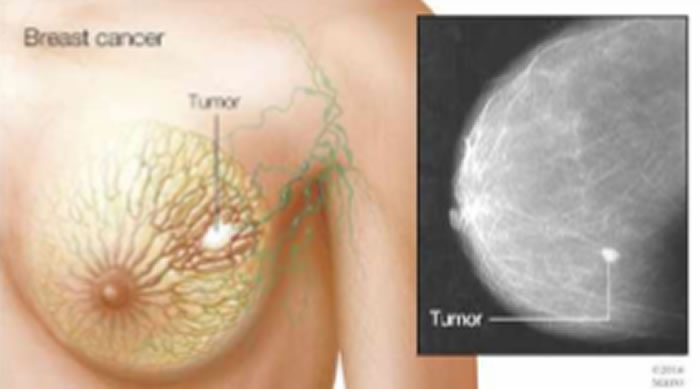

(蜘蛛网eeook.com报道)据EurekAlert!:明尼苏达州罗切斯特 -- Mayo Clinic研究人员发现,一种用于治疗血癌的药物可能对治疗三阴性乳腺癌也有效果。 三阴性乳腺癌是最具攻击性和致命性的乳腺癌(breast cancer)之一。 该研究(study)发表在《临床研究杂志》(Journal of Clinical Investigation)上。

该研究发现,经美国食品和药物管理局批准用于治疗某些血液癌症的药物5-氮杂-2’-脱氧胞苷(地西他滨)可显著抑制三阴性乳腺癌(包括对化疗有抗性的肿瘤)的生长,这种反应取决于某种被称为DNA甲基转移酶蛋白的关键蛋白的存在,该蛋白仅存在于一部分三阴性乳腺癌中,而这提供了一种方法来确定哪些患者可以从该治疗中获益。